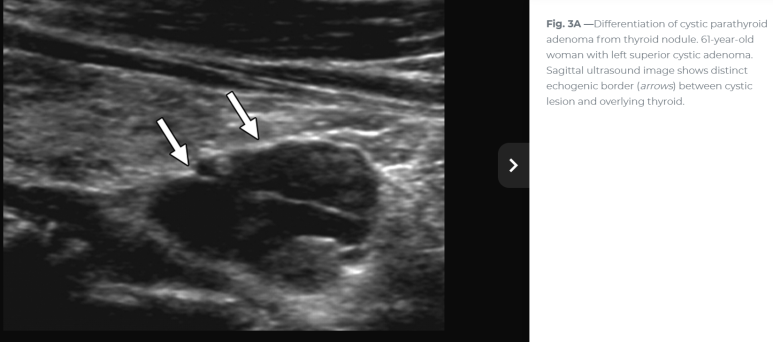

이번 사례와 같은 위치에 비슷한 모습

For nonfunctional parathyroid cysts, which are usually large simple epithelial cysts, the sonographic features are unlikely to add much specificity to the diagnosis. The primary role of ultrasound in these cases is to guide cyst aspiration for PTH assay to confirm parathyroid origin and potentially for therapeutic intervention. 비기능성 낭종일 경우 초음파의 주된 역할은 부갑상선 기원을 확인하기 위해 PTH assay를 위해 낭종 흡인을 보하는 것이다.

Ultrasonography is considered to be the first line imaging modality as part of the diagnostic workup. The sensitivity and specificity of this is operator-dependent but is likely to reveal a cystic nodule that can often be difficult to differentiate from a thyroid cyst 크기가 크면? 갑상선 낭종과 구별이 어려울때도. The absence of comet tail artefacts, which, if present, would indicate a colloid cyst, as well as the lack of other cystic lesions within the thyroid lobes may raise the suspicion of a parathyroid origin. However, differentiation of parathyroid cysts from thyroid cysts based on radiological findings is challenging.